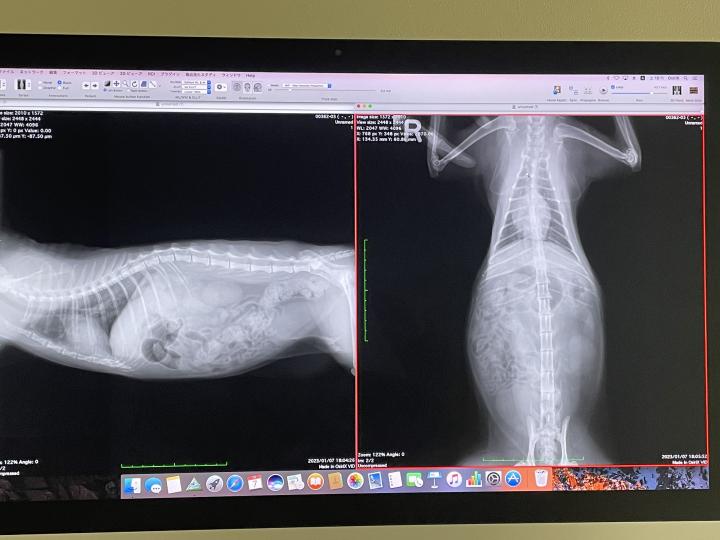

脱水気味だと先生が言っていたこともあり、再度麻酔をかけて検査することに。

血液検査、エコー等やっていただきました。

結果

便がたまってはいるけど

内臓に重篤な疾患は見当たらず